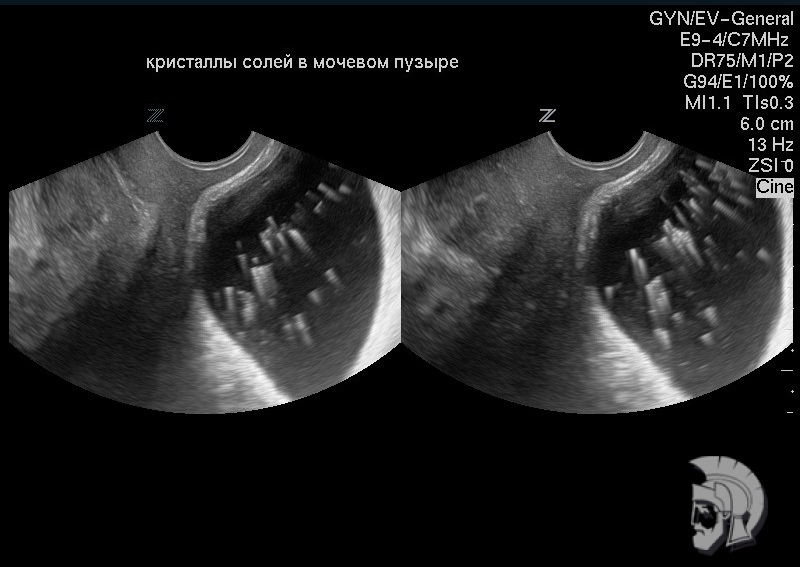

| Фото мочевого пузыря. Кристаллы солей в мочевом пузыре |